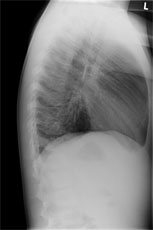

Zur Aufnahme kommt ein 8 jähriger Knabe mit hartnäckigem, vorwiegend trockenem Reizhusten seit 5 Tagen und subfebrilen Temperaturen bis mässigem Fieber.

Bei relativ blander Klinik wird ein Thoraxröntgen durchgeführt:

Thorax seitlich

Bild vergrössern